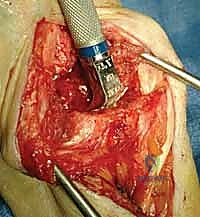

A longitudinal dorsal incision, positioned slightly radial to the midline, is made extending from approximately 4 cm proximal to the radiocarpal joint down to the midpoint of the third metacarpal shaft. Sharp dissection is carried down through the subcutaneous tissues to the level of the extensor retinaculum, taking meticulous care to identify and protect the sensory branches of the superficial radial nerve and the dorsal sensory branch of the ulnar nerve. The third dorsal compartment is opened, and the extensor pollicis longus (EPL) tendon is exposed, mobilized, and retracted radially. The retinaculum is then elevated as a continuous flap. The radial wrist extensors (ECRL and ECRB) are exposed and mobilized radially, while the first compartment tendons are mobilized from the distal radius and protected. The tendons of the fourth and fifth compartments are mobilized ulnarly, ideally without opening their respective synovial compartments to prevent postoperative adhesions.

With the extensor tendons mobilized and safely retracted, a longitudinally based capsulotomy is performed. The capsule is reflected as radially and ulnarly based full-thickness flaps, exposing the distal radius and the entire carpus down to the base of the third metacarpal. Preparation of the distal radius involves scoring a reference line to ensure the DRUJ is preserved. The radial canal is sequentially broached to accept the modular radial stem. The modular radial stem component is designed to fill the distal radius canal to prevent loosening and provide rotational stability. While approved for implantation with bone cement (PMMA), most modern wrists are implanted with press-fit, cementless fixation to encourage osteointegration. Cement is generally reserved for cases of significantly compromised bone stock, severe osteopenia, or revision scenarios.